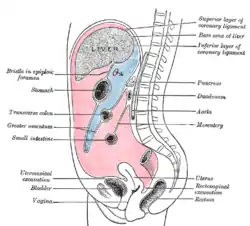

Omental cake is a radiologic sign indicative of an abnormally thickened greater omentum.[1] It refers to infiltration of the normal omental structure by other types of soft-tissue or chronic inflammation resulting in a thickened, or cake-like appearance.[2]

Typically, it is caused by infiltration of metastatic tumors arising from the stomach, ovary, or colon. This dissemination of cancerous cells that do not originate from the omentum itself is called peritoneal carcinomatosis. It can occur other regional tumors such as lymphoma where it is associated with regional lymphadenopathy.[3] It can also rarely occur as a result of infectious causes such as tuberculous peritonitis, peritoneal coccidioidomycosis, and histoplasmosis.[4]

For the most common cause, peritoneal carcinomatosis, omental caking is associated with a wide variety of symptoms. Ascites and intestinal peristalsis is known to have an effect on how diffusely the cancer cells are spread throughout the abdomen. This wide range of presentation makes omental caking difficult to diagnose based on symptoms alone.[5]

Due to the variety of symptoms experienced by patients with omental caking,[5] omental cakes are most frequently discovered on abdominal computed tomography (CT) or ultrasound. Plain film radiography (X-ray) is not a suggested modality for investigating the spread of cancerous cells in the abdomen due to the poor spatial resolution amongst soft-tissue densities. Contrast resolution obtained through CT allows radiologists to investigate omental caking for morphology, intraperitoneal fluid, and regional lymphadenopathy assists in proper diagnosis so clinicians, surgeons, and oncologists can plan the appropriate course of treatment.[8]